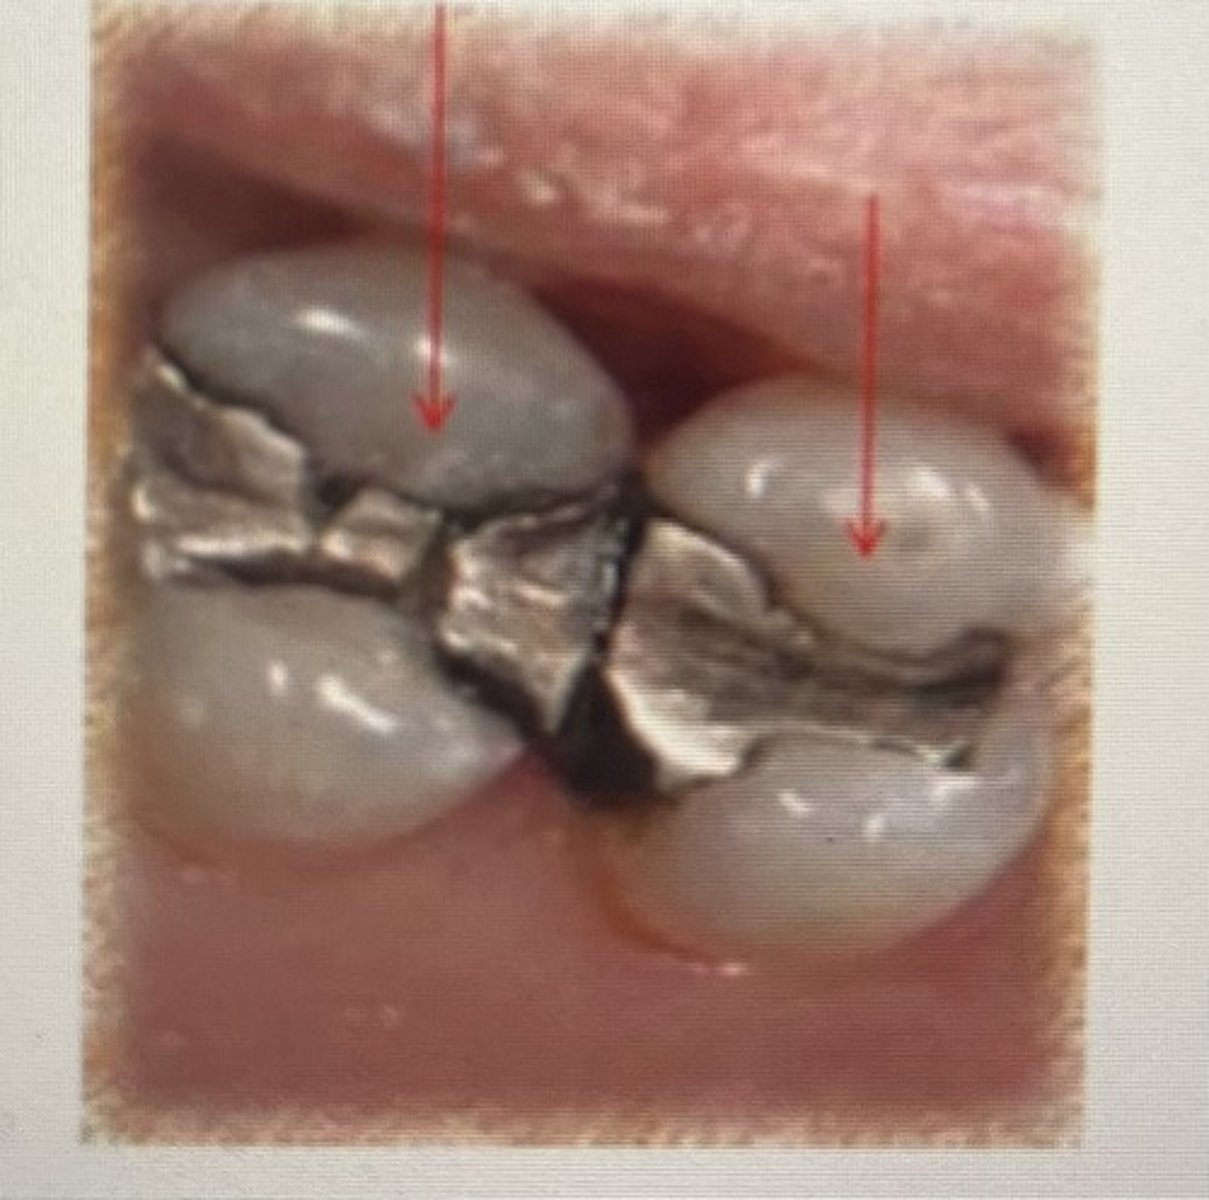

class II restoration